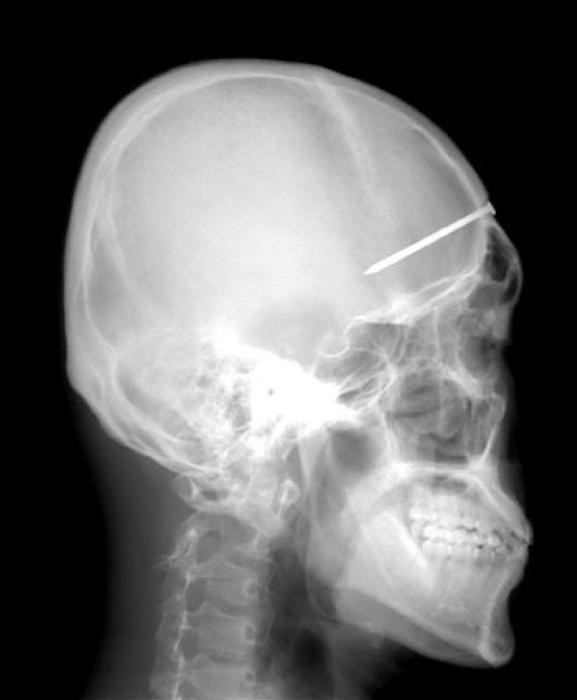

33 radiographies qui prouvent que les gens font des choses douteuses avec leur corps !